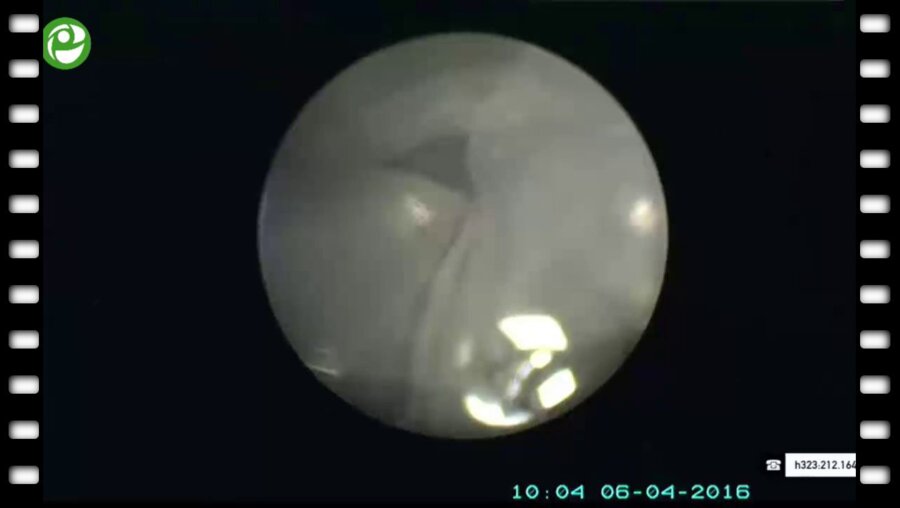

Мастер-класс по перкутанному лечению камней почки

06 апр 2016

3096 просмотров